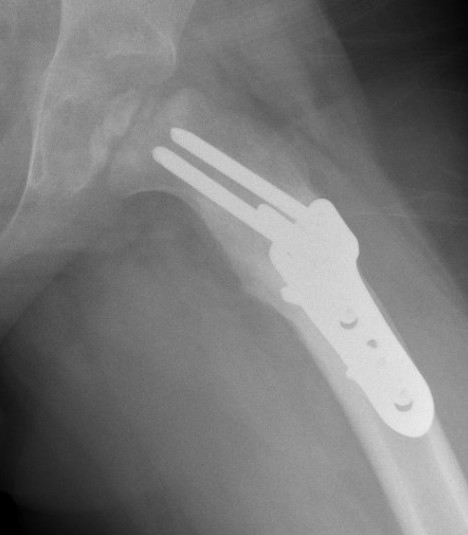

Femoral Varus Osteotomy (FVO)

Indications

Herring grade B or B/C

> 8 years at age on onset

Full containment of cartilaginous head

No hinge abduction

Technique

Synthes Pediatric Proximal Femur Offset Plate Technique PDF

Patient supine on radiolucent table

- preop antibiotics

- frog leg laterals when needed

Lateral approach

- elevate vas lateralis +/- release proximally with L shaped release

- mark distal and proximal femur with drill holes to check rotation

- place wires up femoral neck short of physis

- use plate to mark osteotomy site

Osteotomy with microsagittal saw 1 cm below lesser tuberosity

- aim for 115o of varus

- avoid excessive varus < 100o to keep greater trochanter distal to femoral neck

- +/- adjust version

- apply plate and fix with screws